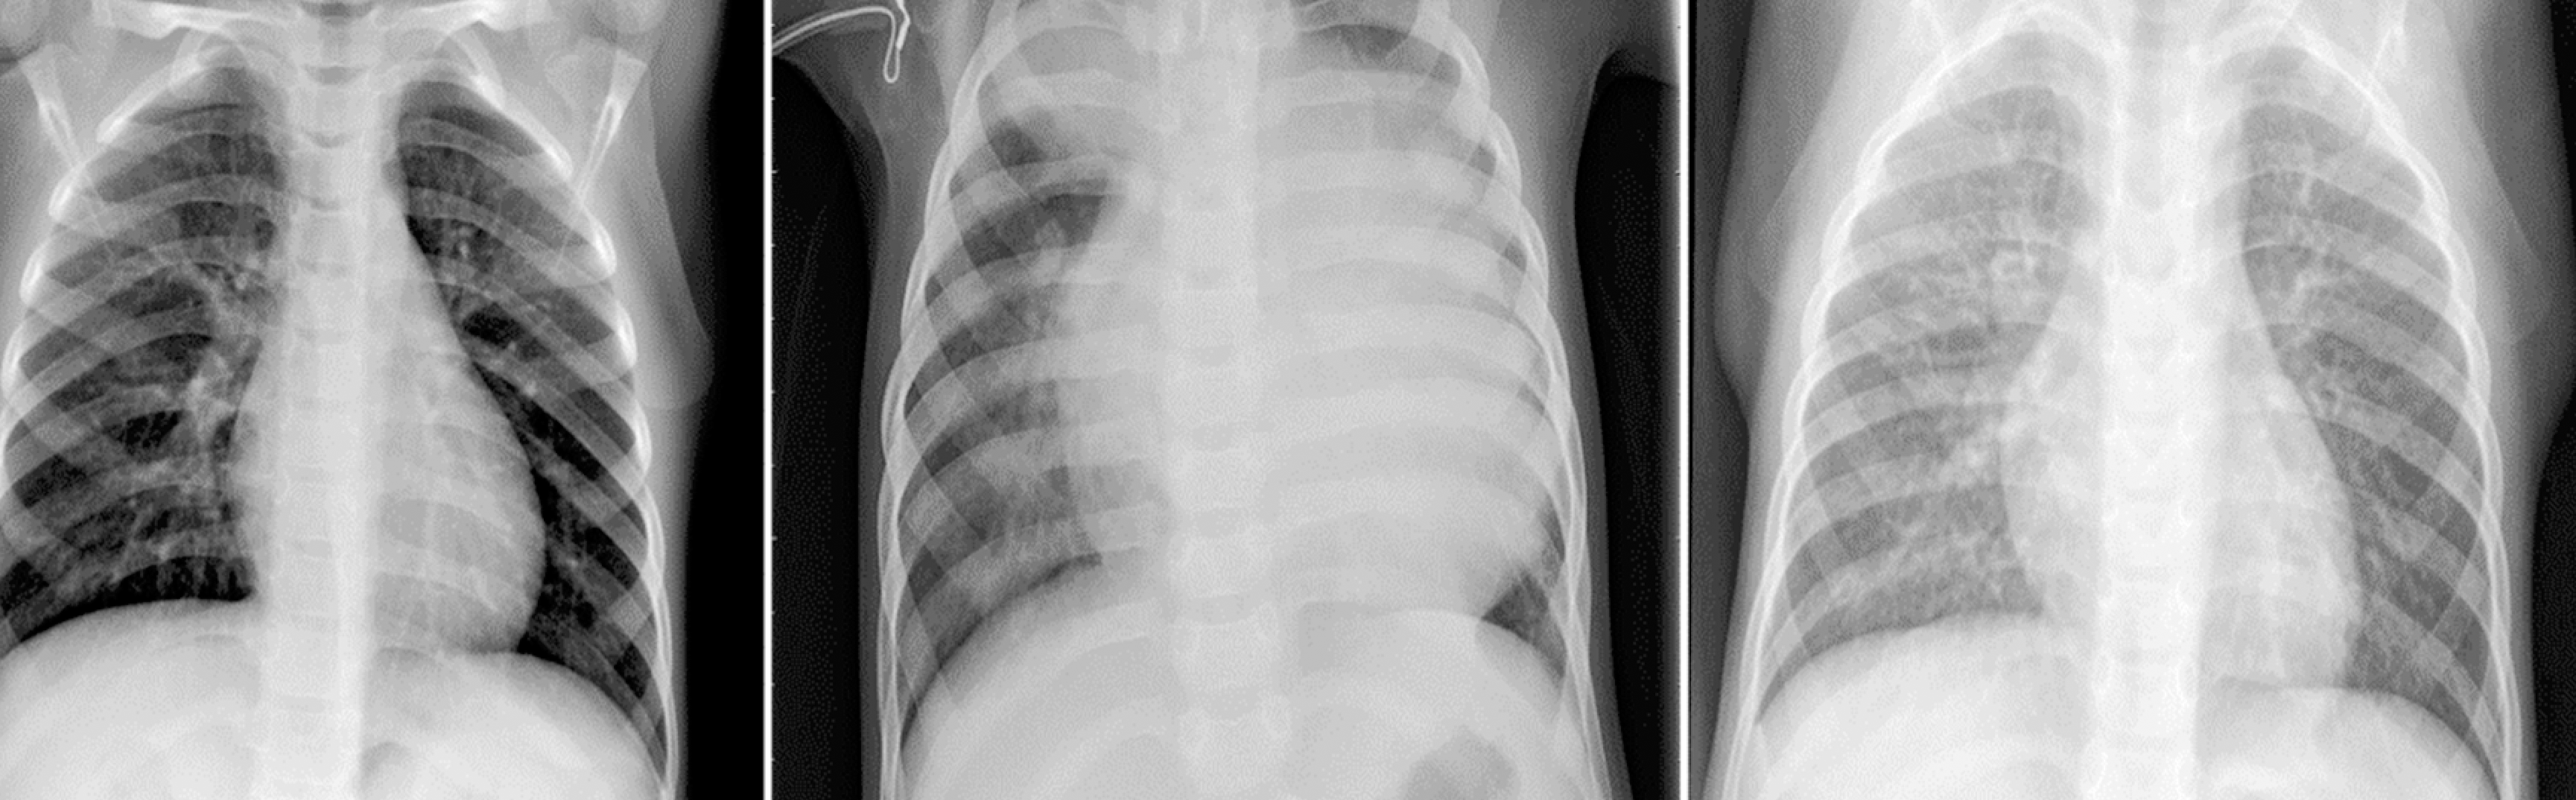

During my studies I've decided to use deep learning neural networks to build an algorithm that classifies a set X-rays images belonging to pediatric patients to help determine if whether or not pneumonia is present. The goal is to help the patient by knowing sooner than later if pneumonia is present so that treatment could begin promptly. The Neural Network I've chosen was the Convolutional Neural Network (CNN) since it is highly preferred for image processing.

For my project I've used data sourced from kaggle.com. Upon initially exploring the data, I noticed it contained 5,756 X-ray images.